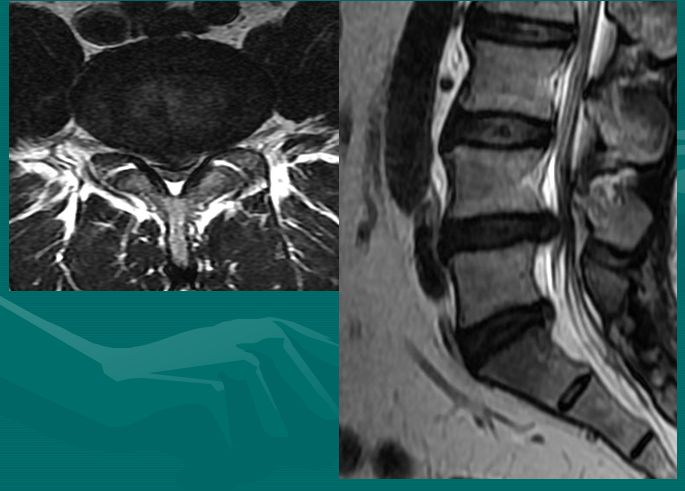

在此图中,可清楚地看到悬挂在硬膜囊内的细小的神经根(L5神经根及S1神经根),它们以不完全有绪地状态排列着。注意,神经孔是很开阔的(浅黄色区),表明没有因邻近椎间关节问题形成在的椎管狭窄。T2加权象对于察看退化性椎间盘病是最好的,因为T2像将富含水份的结构表现为亮白色, 含水少的区域表现为黑色。

位于椎体之间的椎间盘应是白色的(含水多)。注意黑颜色(脱水的)的L5椎间盘(L5与骶骨之间的椎间盘),这代表了中度到重度的退化性椎间盘病。

后纵韧带(PLL小蓝箭头)在图像中表现为沿着每个椎体及椎间盘后缘垂直向下的黑线。有意思的是,尽管此病人有一个9mm的椎间盘突出(HNP),骨质有一定的翘起,在椎间盘平面以上可见髓核物,但后纵韧带仍然包容着突出的髓核物而没有游离出。这种情况在学术上被称作一个大的包容性椎间盘突出。

硬膜囊(红星)表现为“超白色”结构,填充在椎体后方的中央椎管内。此囊袋内有可自由浮动的由运动神经纤椎及感觉神经纤维共同组成的脊神经根(马尾)。

黄韧带(绿星)位于每个椎骨之间,增强脊柱的稳定性。此结构可变大或增厚,助长年长者易患的中央型椎管狭窄的形成。